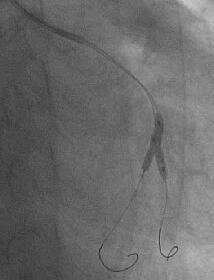

姤摦柆僀儞僞乕儀儞僔儑儞丗僈僀僨傿儞僌僇僥乕僥儖偺engage偑埆偄偨傔丄儔僕

僆僼僅乕僇僗丒儚僀儎乕偱僇僥乕僥儖傪屌掕偝偣側偑傜彊乆偵儚僀儎乕傪恑傔偰

偄偔偲丄彮偟偯偮寣娗偑憿塭偝傟傞傛偆偵側傝丄恖岺寣娗偲LMT偺暙崌晹偵崅搙

嫹嶓傪擣傔傑偟偨乮Figure4乯丅傑偨丄嵍姤摦柆撪偵嫄戝側寣愷傪擣傔傑偟偨丅

摉帪寣愷媧堷偺僨僶僀僗偑側偔丄媧堷偼偱偒傑偣傫偱偟偨丅暙崌晹偵懳偟偰丄

MAVERICK4.0mm偱POBA傪峴偄丄偦偺屻LAD偵嫄戝側寣愷偑棳傟偰偄偔偺偑妋擣偝傟

傑偟偨乮Figure5乯丅NIR4mm僗僥儞僩傪棷抲偟暙崌晹嫹嶓偼夵慞偟傑偟偨偑丄LAD

偺no flow傪擣傔傑偟偨丅nicorandil偍傛傃UK傪姤拲偟偨偲偙傠丄flow偑夵慞偟

偨偨傔庤媄傪廔椆偟傑偟偨乮Figure6乯丅